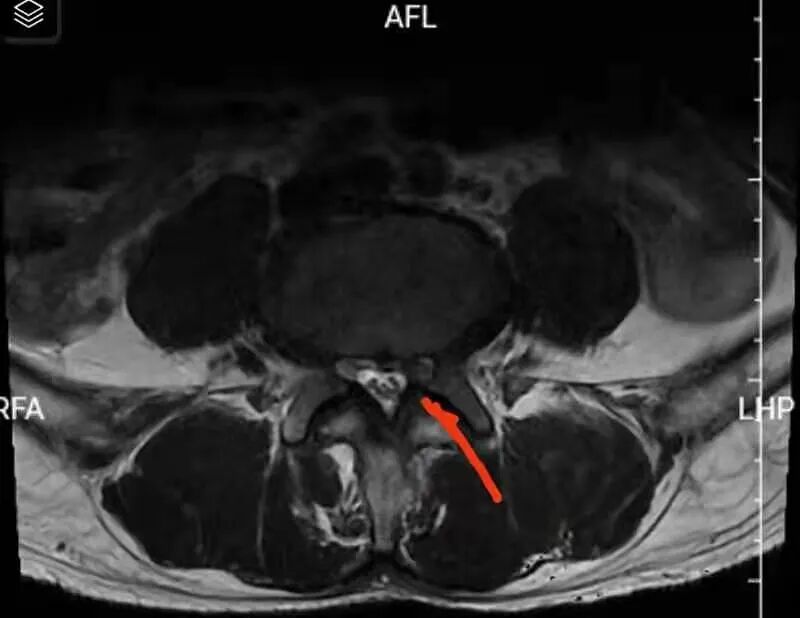

腰椎MRI检查结果提示为腰4/5椎间盘突出压迫神经,临床诊断为腰4/5椎间盘突出症。金博士在与患者沟通时表示:腰椎间盘突出症是较为常见的疾患之一,主要是因为腰椎间盘各部分(髓核、纤维环及软骨板),尤其是髓核,有不同程度的退行性改变后,在外力因素的作用下,椎间盘的纤维环破裂,髓核组织从破裂之处突出(或脱出)于后方椎管内,导致相邻脊神经根遭受刺激或压迫,从而产生腰部疼痛,一侧下肢或双下肢麻木、疼痛等一系列临床症状。而于先生突出的腰间盘碎片很小,这种小的椎间盘突出就好像一个人光着脚走路踩到大的石头不一定会很疼痛,但是踩到又小又尖的小石块会很疼痛一样,所以这种类型椎间盘突出患者往往疼痛感会更加强烈。

红色线条处是碎块很小的突出的间盘